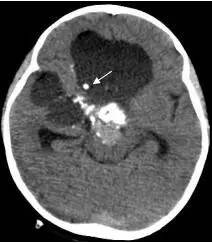

患儿入院后第三天,病情恶化,意识不清,急诊行肿瘤囊穿刺引流术,引流出囊液约200毫升,引流后患儿精神立即好转,肿瘤体积减小,引流手术切口设计及引流后CT见图7、图8。调养7天后在全麻下行开颅手术切除肿瘤,经过10个小时的努力,完全切除肿瘤,术后患儿清醒,语言交流正常,左侧上下肢肌力稍弱。患儿经历一系列的并发症,如电解质紊乱、脑水肿、癫痫发作等,共计住院47天后出院。术后CT见图9。

图8.肿瘤囊引流后体积明显变小

白色箭头显示引流管